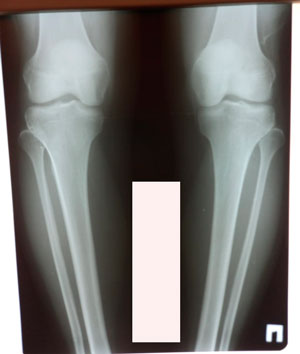

Исходник - 37 лет.

Дата операции - 05.02.2021

image-05-02-21-07-29-4.jpg

image-05-02-21-07-29-1.jpg